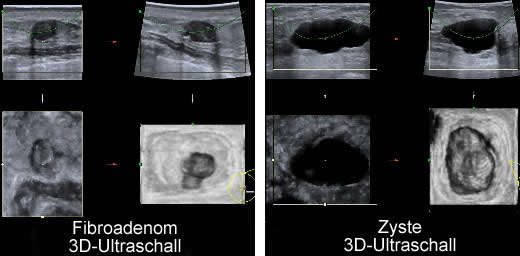

Geschwulst Neoplasma Neubildung Neoplasie auch solche die durch eine Entzündung einen Erguss oder Ähnliches hervorgerufen wurden. Das Wort Tumor bedeutet Schwellung oder Verhärtung auch. Fibroadenom Gutartiger Knoten in der Brust gutartiger Tumor in der Brust Gutartige Knoten sind Verdickungen des Bindegewebes.

Sie entstehen durch Vermehrung von Bindegewebe und Drüsengewebe. Eine Wahrscheinlichkeit einen Tumor mit einer Größe. Es setzt sich aus Drüsengewebe Adenom und Bindegewebe Fibrom zusammen.

Das Fibroadenom ist der häufigste gutartige Knoten der weiblichen Brust. Mediziner unterscheiden folgende gutartige Brusttumoren mit jeweils verschiedenen Eigenschaften. Trotzdem bleiben Zysten meist unbemerkt.